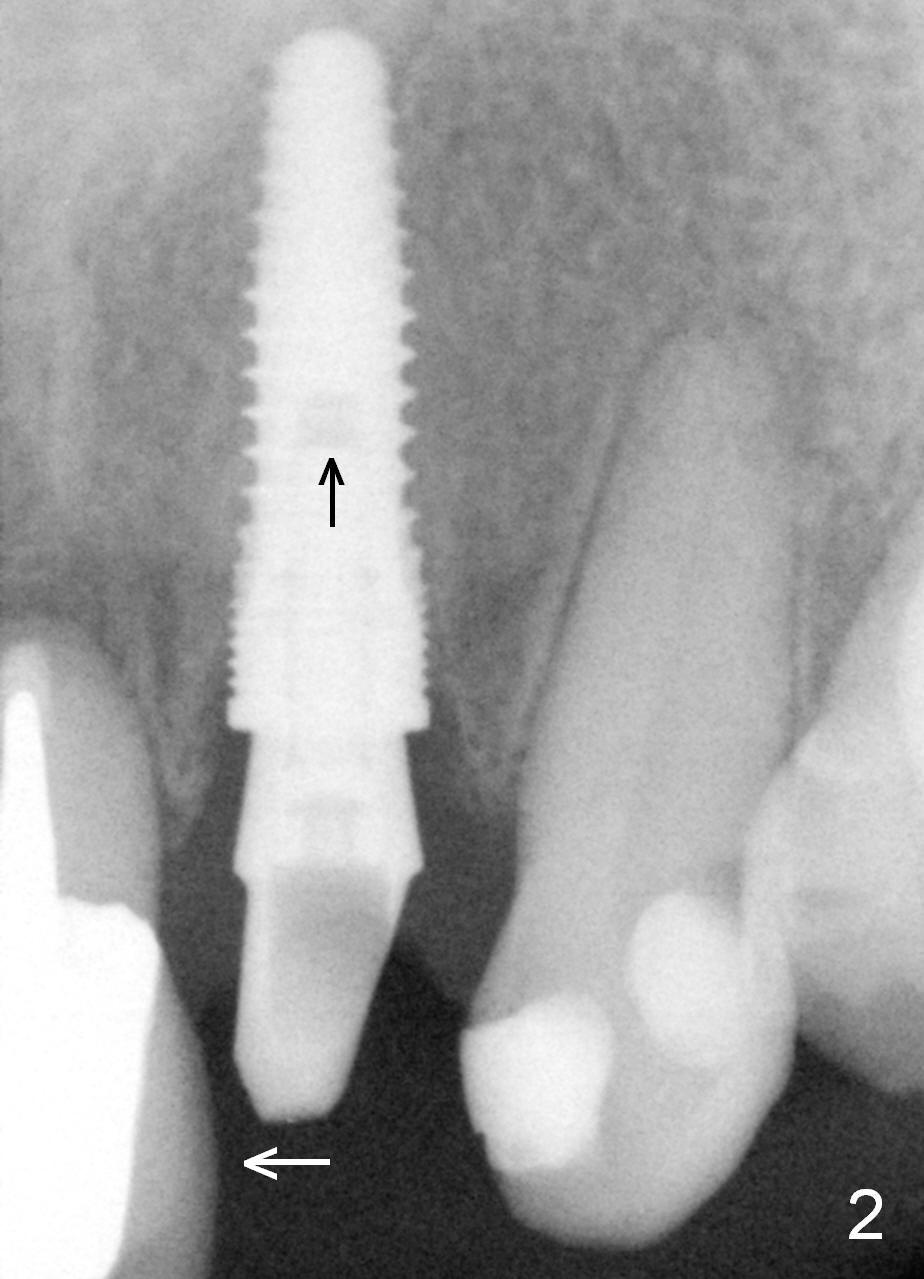

Fig.4, 5 shows shades against the teeth #7 and 10.